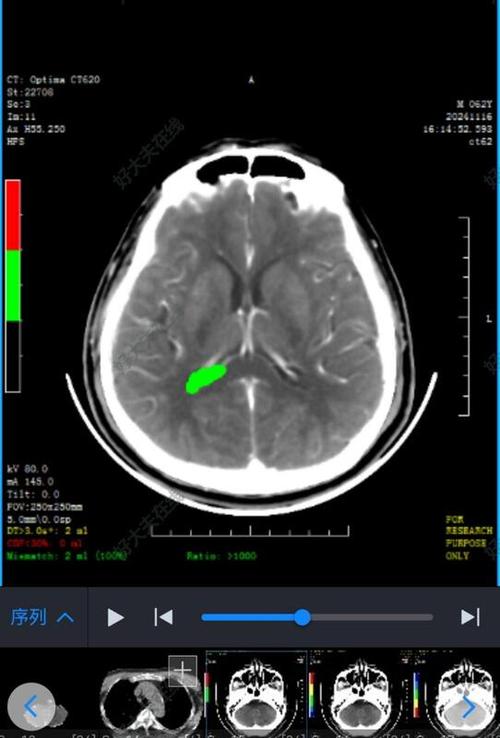

“病灶”是一个非常宽泛的医学术语,它指的是影像学(如CT、MRI)上观察到的任何与周围正常组织结构不同的异常区域,脑梗只是众多可能导致脑CT出现病灶的疾病之一。

当医生说“CT上有个病灶”,他只是在描述图像上有一个异常区域,但需要结合其他信息来判断这个“病灶”到底是什么。

- CT表现:在发病早期(6小时内),CT可能完全正常,或者只有非常细微的改变,这是CT诊断脑梗的一个局限性,通常在发病24-48小时后,梗死区域才会因为脑组织水肿而出现清晰的低密度(变黑)病灶。

- 特点:病灶的形态和分布与脑血管的供血区密切相关。